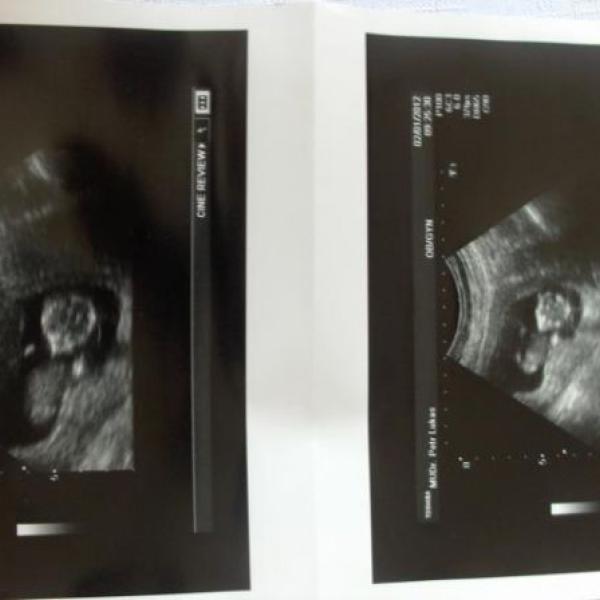

tak vkládám našeho mrňouska...tak mrkněte :)

Ahoj holky, tak se vám hlásím z dnešní kontroly u :*8*: , jsme 8+5, i když mi do průkazky napsal 7+5, ale to se spletl, protože mi to i říkal, že jsme na konci 9, týdne, ale to nevadí, :h: tluče, co